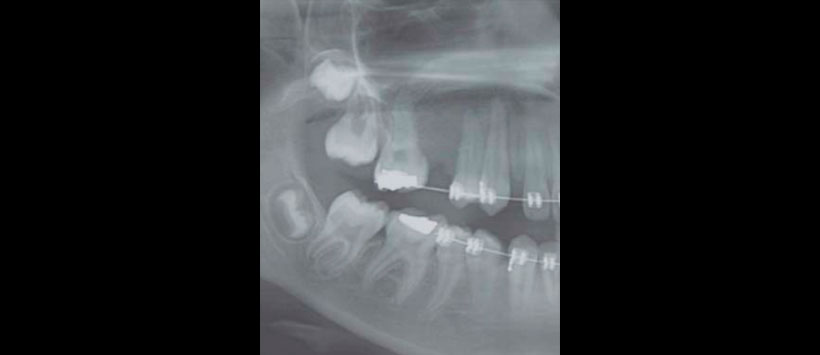

Imagenológicamente en la ortopantomografía se observó una zona radiolúcida unilocular circunscrita bien delimitada, con borde radiopaco bien definido, segundo premolar incluido en posición horizontal. Segundo molar deciduo con tratamiento pulpar. Tomografía de haz cónico: cortes axiales, sagitales, coronales y reconstrucción tridimensional mostraron quiste maxilar derecho de 2.6 cm de diámetro total, ocupando la tercera parte de la capacidad volumétrica de seno maxilar, desplazamiento de la pared anterior de seno maxilar y pared lateral de la fosa nasal derecha (Figuras 4 a 6).